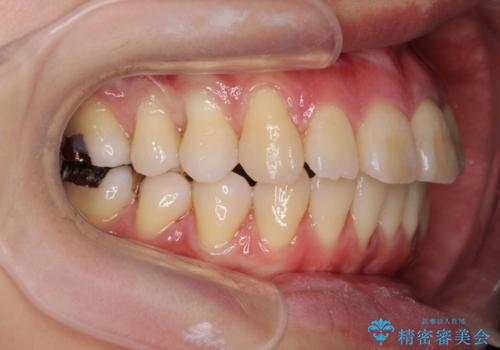

- 出っ歯に見える前歯、捻れてしまった小臼歯の改善を求めて来院されました。

マウスピースでは改善の難しい小臼歯のねじれをまず部分ワイヤー矯正で改善し、その後マウスピース矯正で前歯の突出感を改善します。

時間はかかりましたが、捻れ、かみ合わせ、前歯の角度の改善が達成され満足いただくことができました。